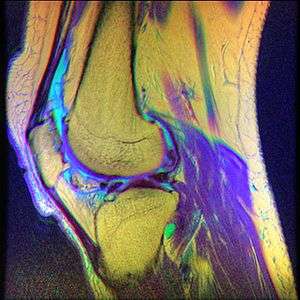

While the term chondromalacia sometimes refers to abnormal-appearing cartilage anywhere in the body,[6] it most commonly denotes irritation of the underside of the kneecap (or "patella"). The patella's posterior surface is covered with a layer of smooth cartilage, which the base of the femur normally glides effortlessly against when the knee is bent. However, in some individuals the kneecap tends to rub against one side of the knee joint, irritating the cartilage and causing knee pain.[7]